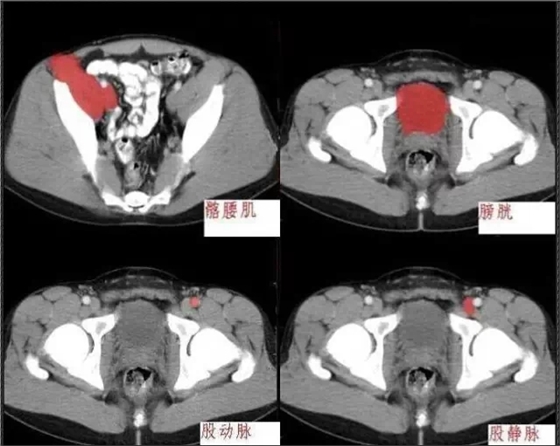

640.webp (6).jpg

640.jpg